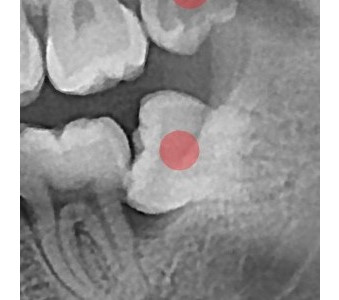

• 03

정확성 높은 치료의 시작 디지털 정밀진단 시스템

3D 디지털 데이터 기반으로 정확성 높고 정교한 치료가 가능합니다.

결과로 증명합니다.

국제모아치과의

실제 임상 증례